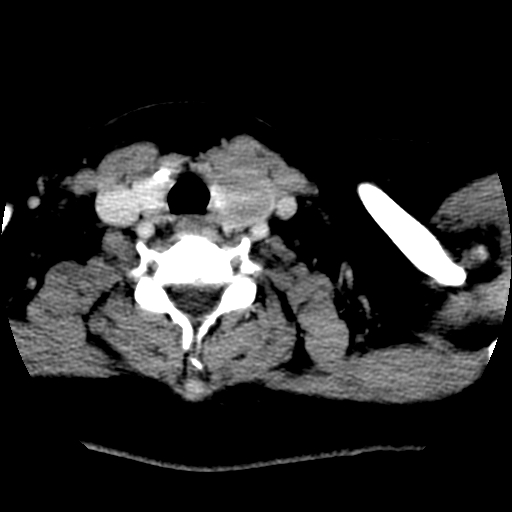

标题: CT25491:女,55岁,发现左侧甲状腺肿块一个月。 [打印本页]

女,55岁,发现左侧甲状腺肿块一个月,彩超示:甲状腺多发结节伴左叶结节液化。

考虑左侧甲状腺结节性甲状腺肿,不排除甲状腺腺瘤。